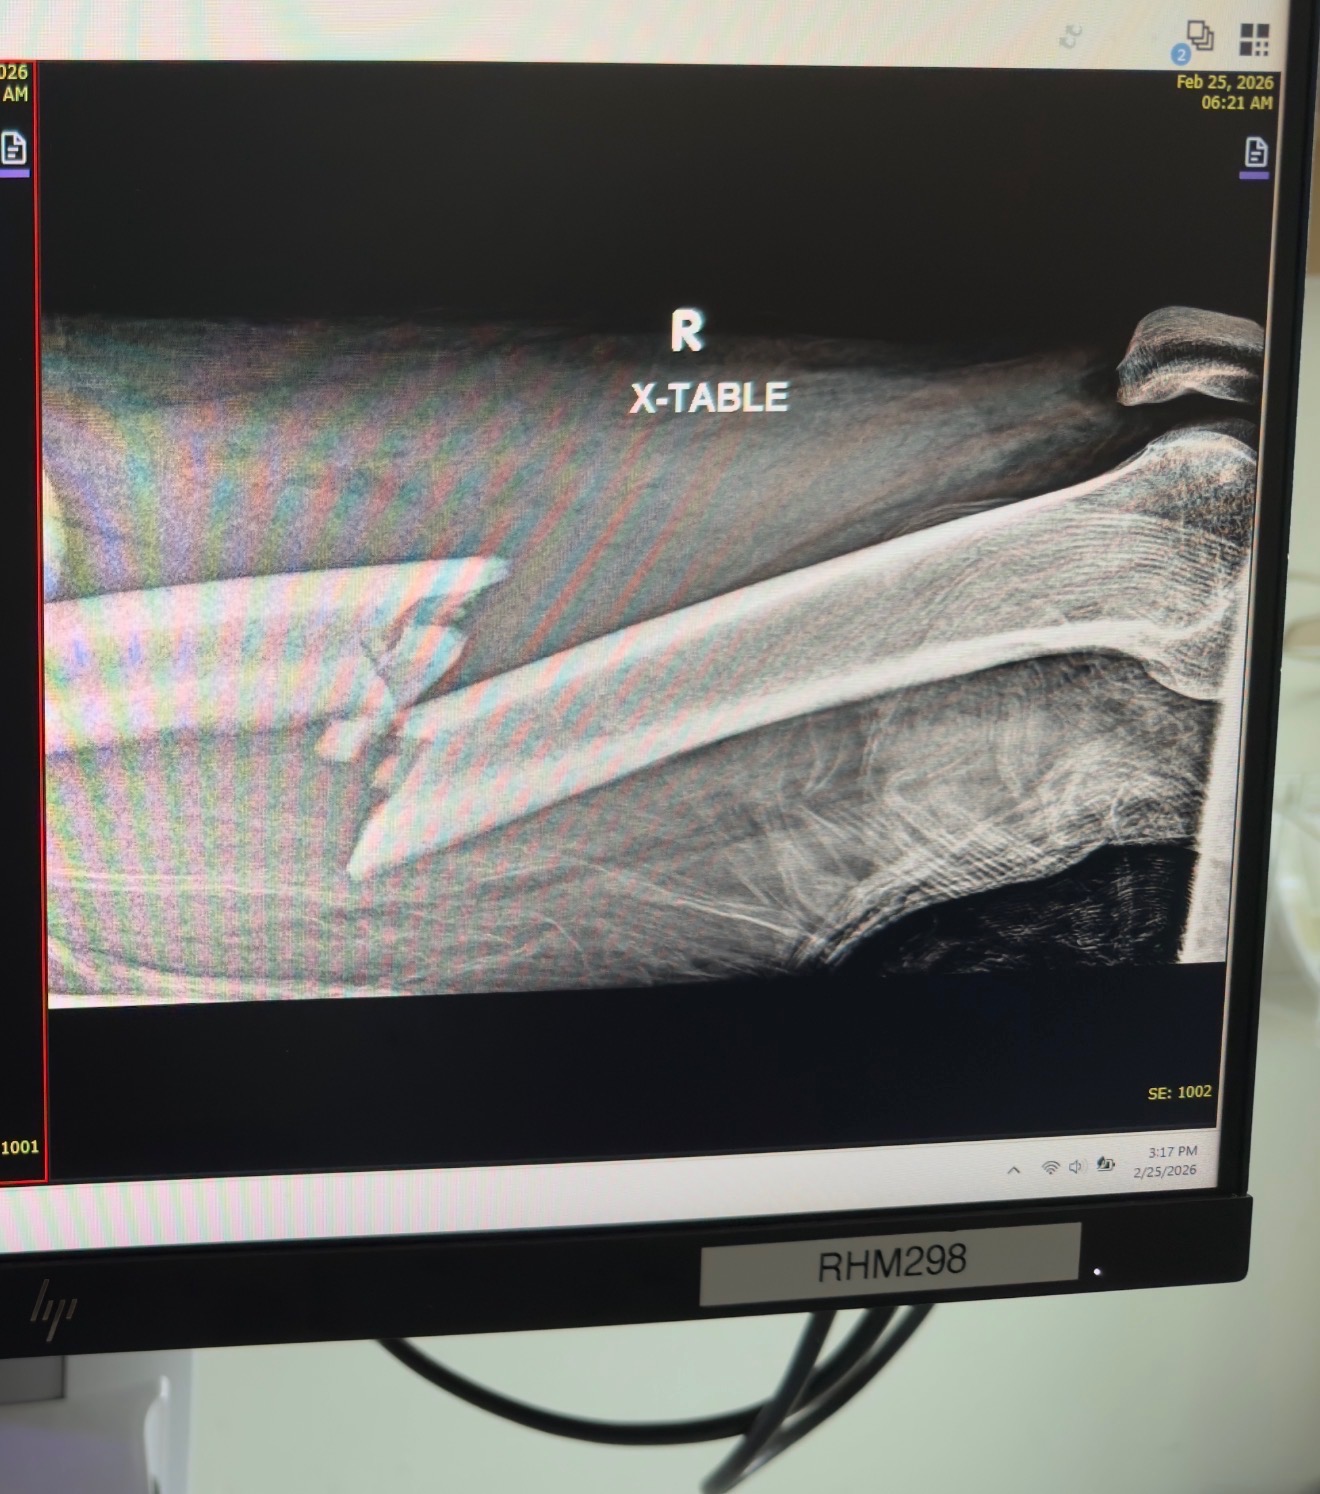

Hi it’s Travis Jeff’s bro in law, and I’m reaching out for help for Jeff horst and family. unfortunately he had a snowmobile crash and broke his right femur and his left wrist. He will be off of work for a while and could use all the help he can get thank you everyone!!